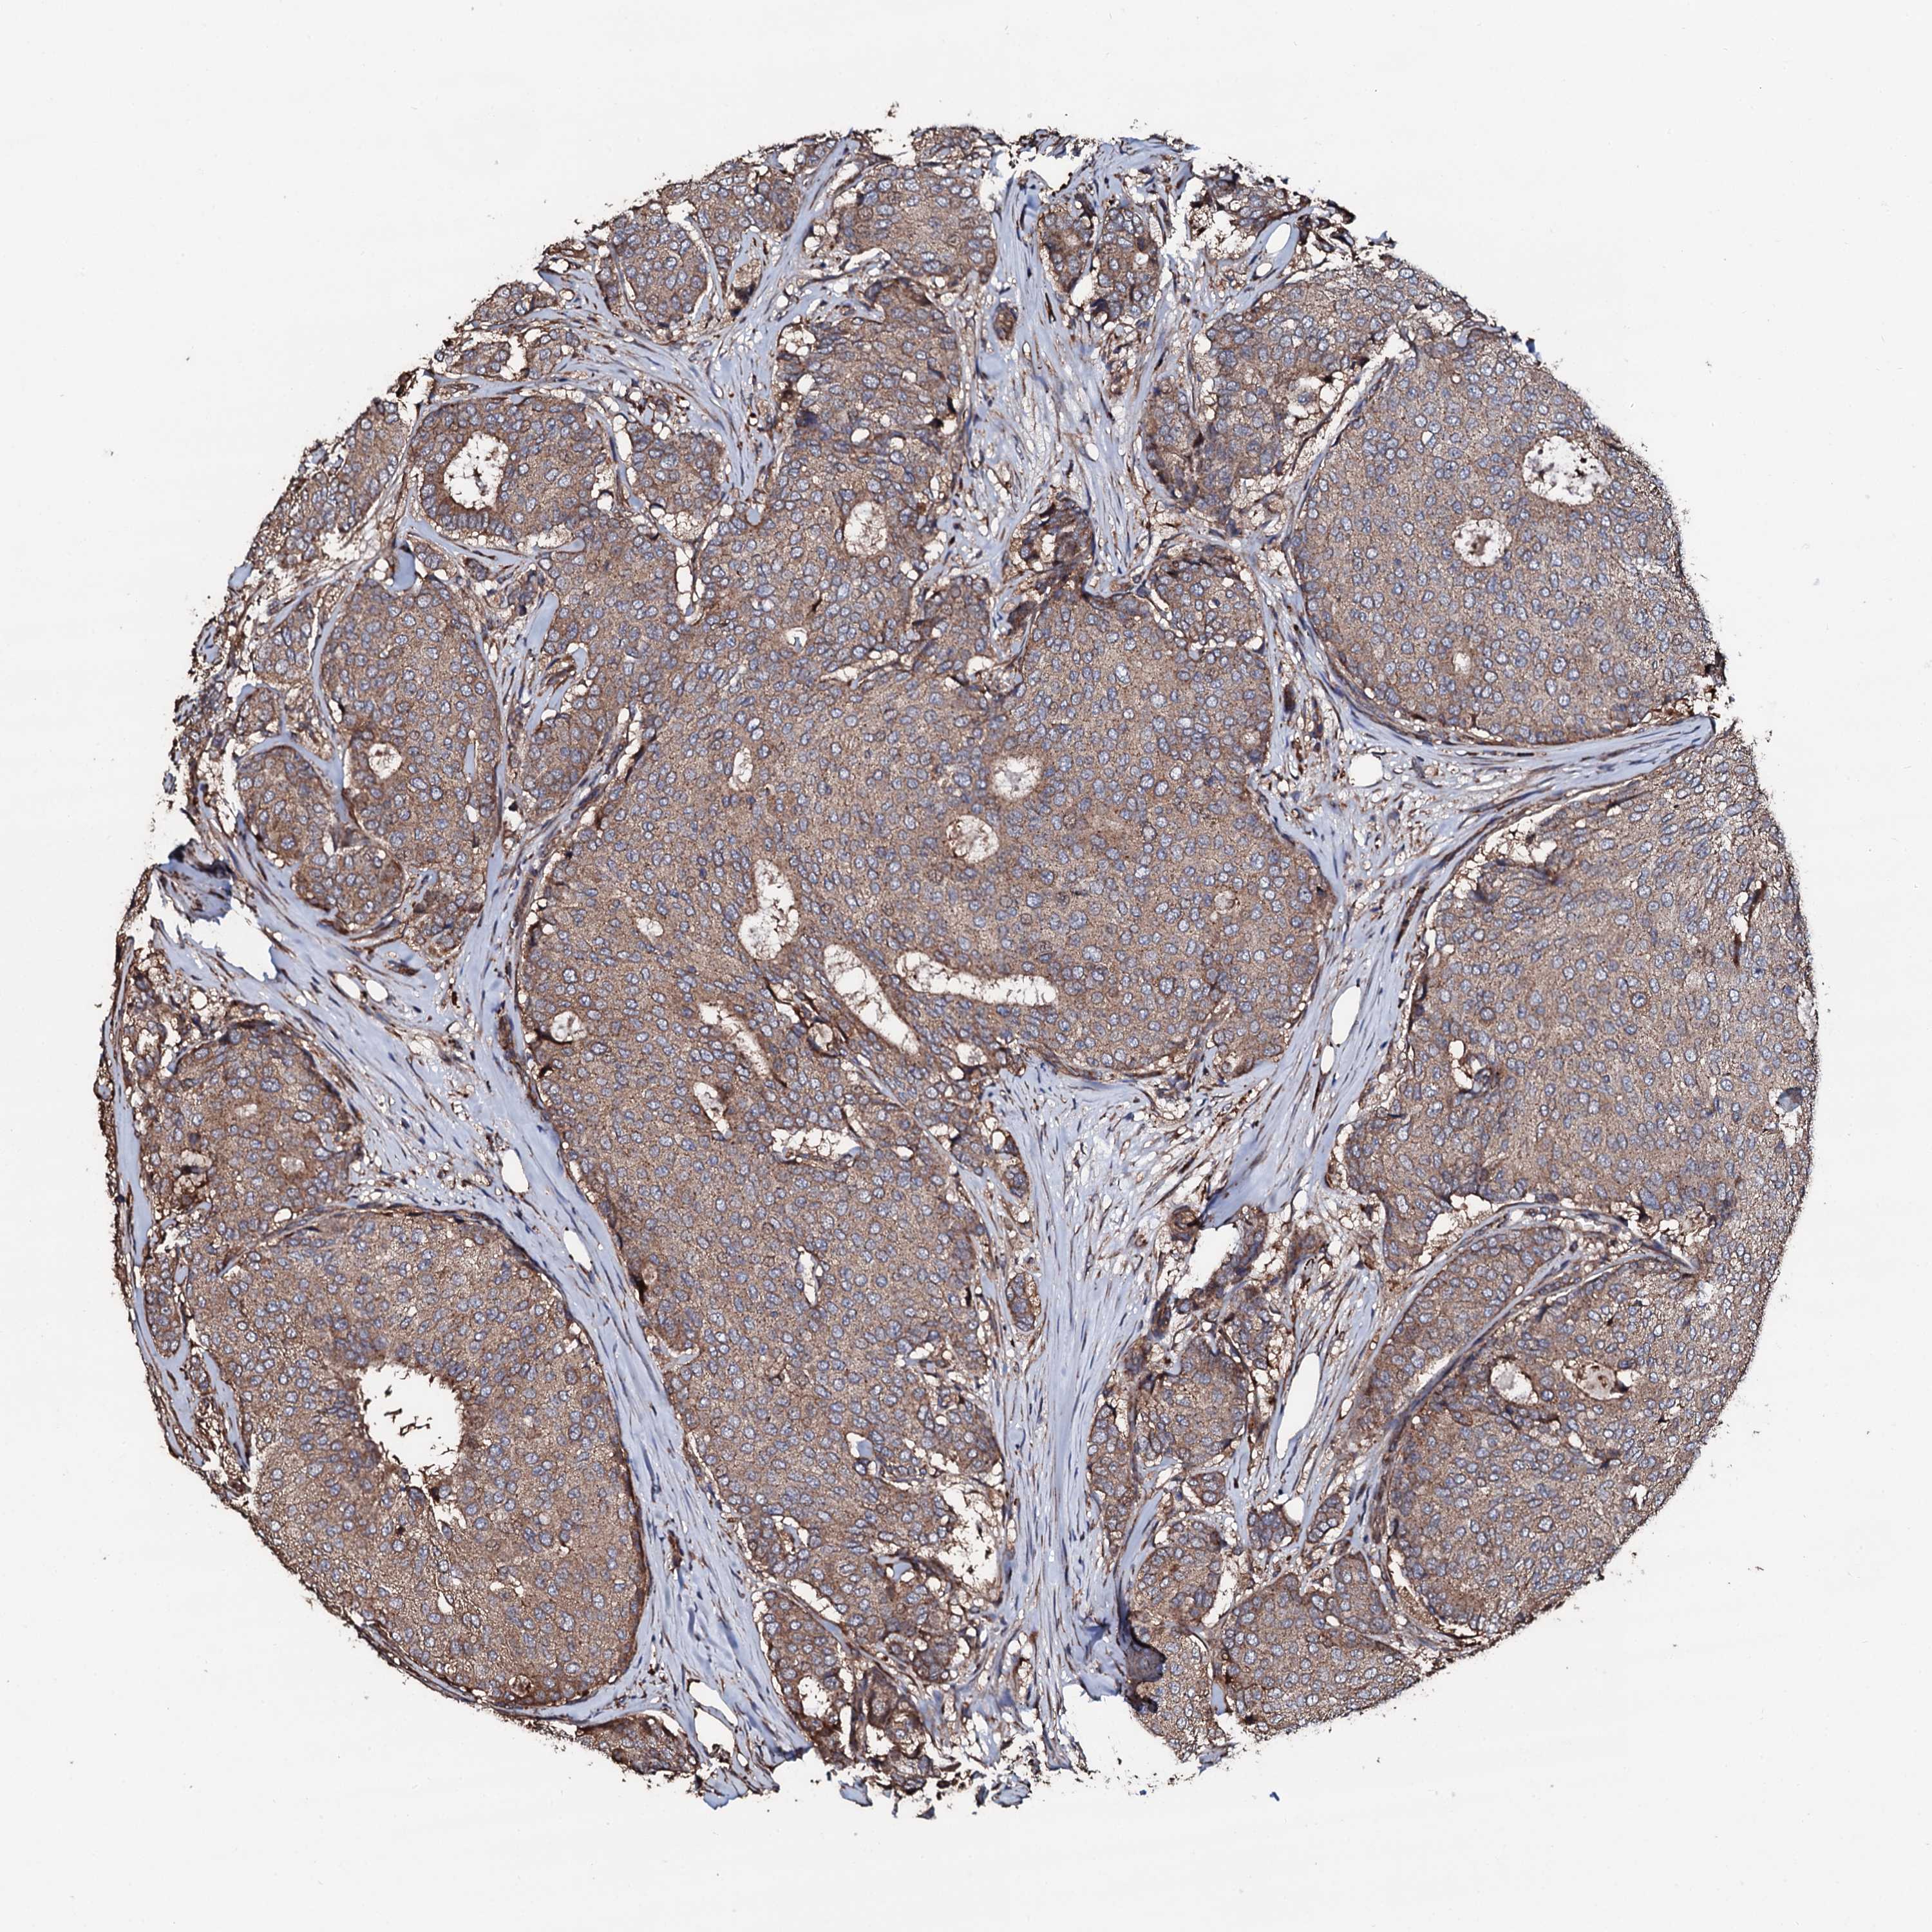

CANCER BREAST CANCER Show tissue menu

BRCA TCGA BRCA VALIDATION PROTEIN EXPRESSION